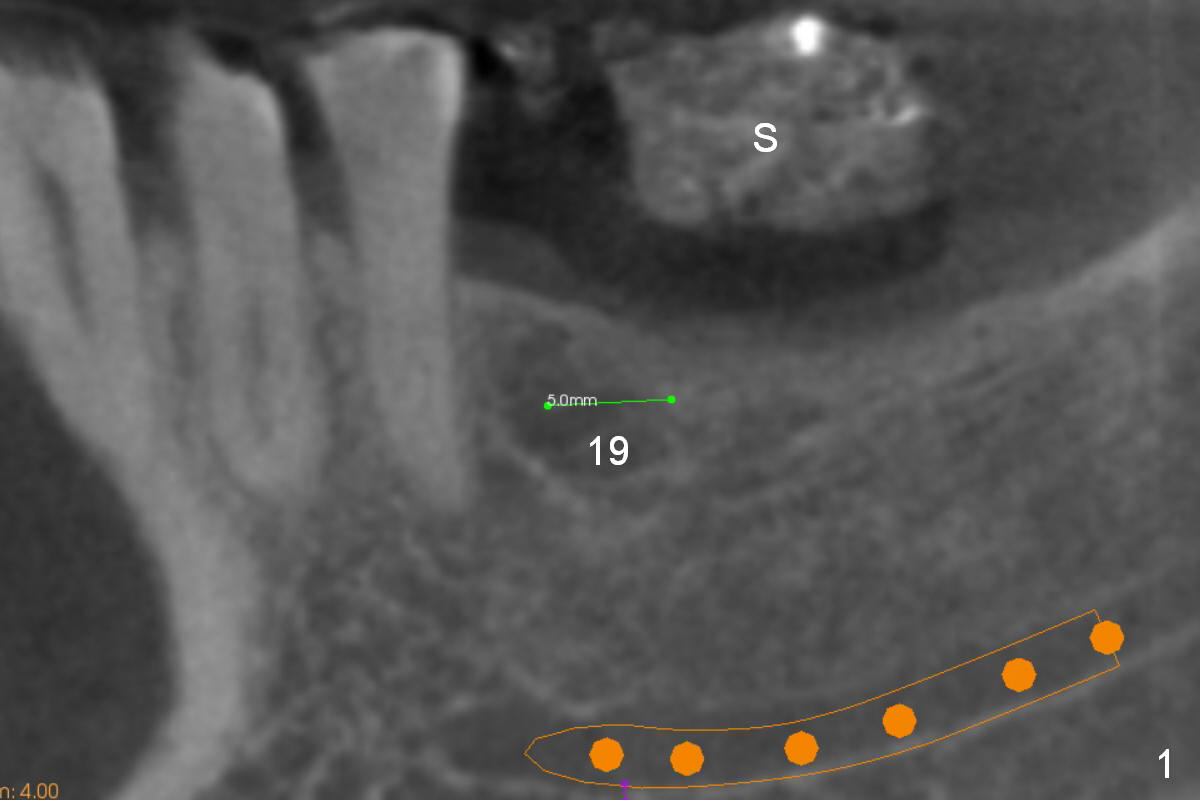

Pointed Ridge at #19

A 56-year-old man decides to have an implant at #19 after those at #13 and 14 (Fig.1 (S: CT stent)). The coronal section shows the pointed ridge (Fig.2 *). For easy implant placement and reduction in thread exposure, the ridge will be trimmed flat (Fig.3 (black area), or more exactly (funnel shaped Fig.4 (arrowheads to accommodate the shape of the cemented abutment (pink)) or concave (Fig.6)). After placing a 5x10 mm UF implant (green), bone graft to be placed (Fig.5,7 red circles) remains in place followed by collagen dressing (Fig.7 yellow lines).